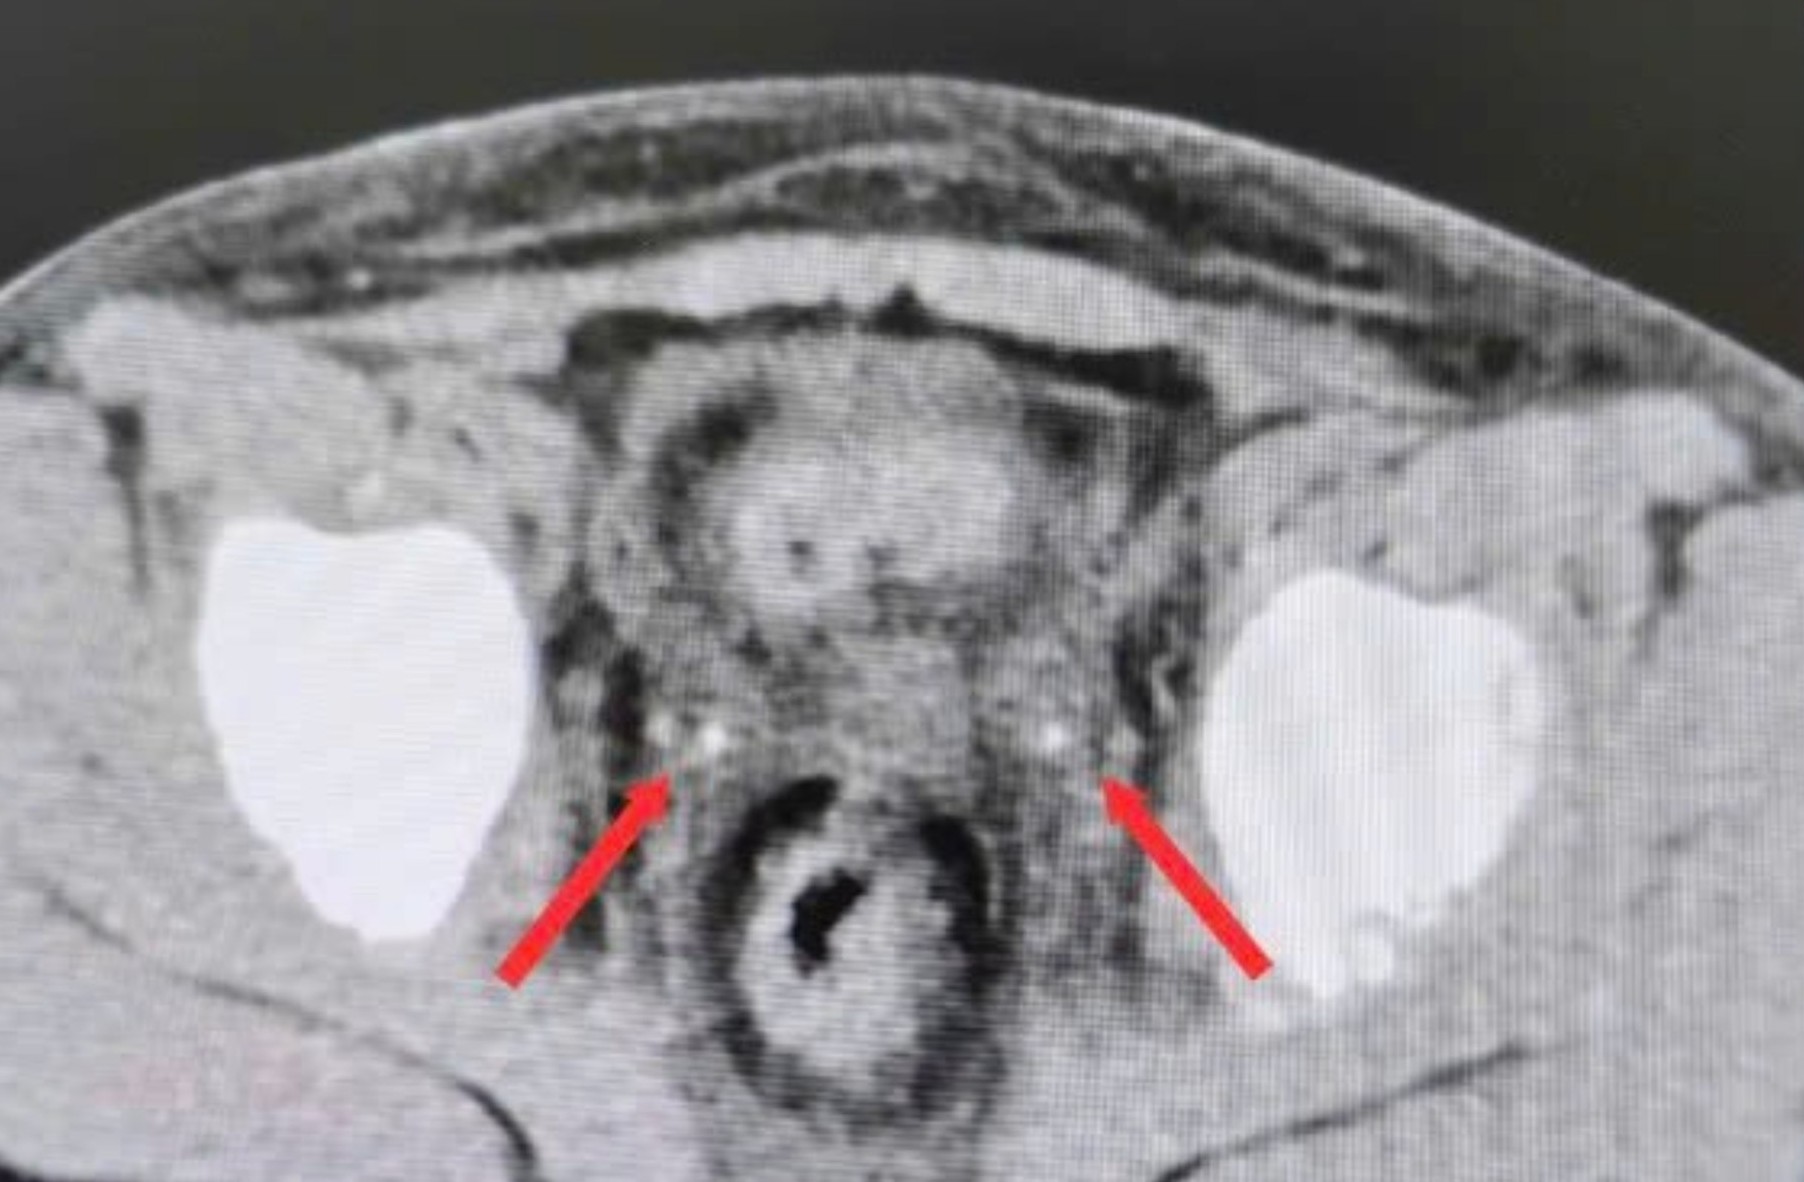

PNO - Trong giai đoạn hậu phẫu viêm ruột thừa, bé trai được phát hiện tổn thương thận cấp do kẹt sỏi niệu quản.